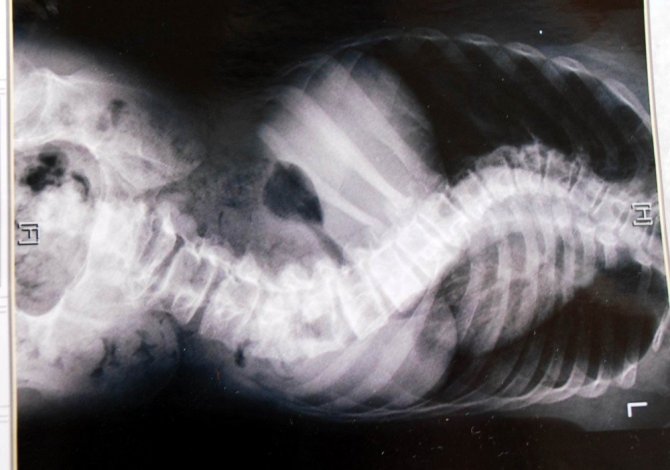

Manisa’nın Salihli ilçesinde bebekliğinden bu yana epilepsi nöbetleri geçiren Mine-Orhan Uysal çiftinin tek oğlu Ahmet Uysal, 15 yaşında geçirdiği nöbet sonrası, omurga eğriliğinin artması nedeniyle yürüyemez hale geldi.

15 yaşından bu yana hem yürüyemeyen hem de konuşamayan Ahmet Uysal’ın omurga eğriliği iyice artınca, bu kez de kaburgaları akciğer ve kalbine baskı yapması sonucu nefes alıp vermekte zorluk çekmeye başladığını anlatan anne Mine Uysal, "Oğlum 15 yaşında geçirdiği nöbet sonrası omurga eğriliğinin (skolyoz) birden ilerlemesi sonucu yürüyemez hale geldi. Şu an hiç yürüyemiyor. Oğlumuzu tedavi ettirmek istiyoruz, bunun için de acilen ameliyat olması gerekiyor. Şu an kaburgaları eğrilikten dolayı kalbi ve ciğerlerine baskı yapıyor. Bundan dolayı da rahat nefes alıp veremiyor” dedi.

Doktorların oğullarının acilen ameliyat olması gerektiğini söylediklerini belirten Uysal, “Ankara İbni Sina Hastanesi’ne gittik. Orada da çok acil ameliyat olması gerektiğini ve bunun için de beklememiz gerektiğini söylediler. Şu ana kadar henüz geri dönüş olmadı. Bu geri dönüşün bize çok acil olmasını bekliyoruz. Çünkü oğlumun çok acil ameliyat olması gerekiyor” diye konuştu.